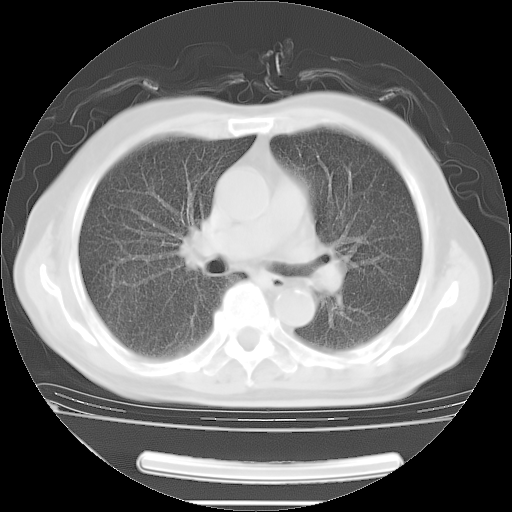

5月9日肺部CT(在4月27日齐鲁医院肺部CT描述部分肺组织磨玻璃样改变,12天后肺组织广泛磨玻璃样改变)

2009年5月9日肺部CT

大致读了系列胸部CT:纵隔窗无明显异常,肺窗:从4、27至今:主要是双肺中下野外带可见毛玻璃样改变,目前处于急性肺泡炎阶段,至于原因考虑1、结替组织或胶原血管性疾病所致?2、恶性疾病如恶组在肺部所致的表现或细支气管肺泡癌?3、药物或其它原因如肺蛋白沉着症所致肺泡炎目前不太可能?总之,明天就去请我院的呼吸科、感染科、血液科和临免专家会诊哈。